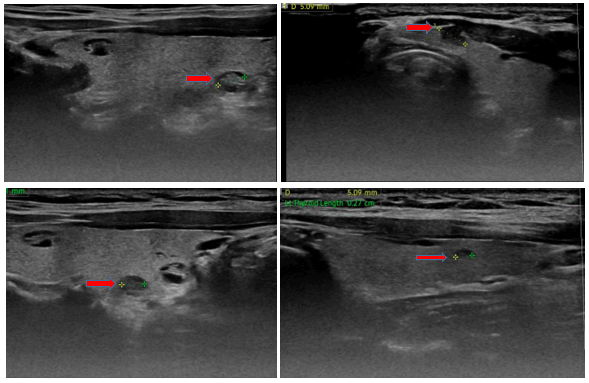

-    Siêu âm tuyến giáp (trước mổ): Hình ảnh nhân giảm âm thùy phải và eo tuyến giáp khoảng 5mm (TIRADS 4). Nhân hỗn hợp âm thùy phải tuyến giáp (TIRADS 3). Dưới cằm lệch phải có vài hạch, kích thước lớn nhất 7mm, cấu trúc bình thường.

Hình 2: Hình ảnh siêu âm tuyến giáp và vùng cổ có nhân giảm âm thùy phải và eo tuyến giáp khoảng 5mm (TIRADS 4), (mũi tên đỏ)